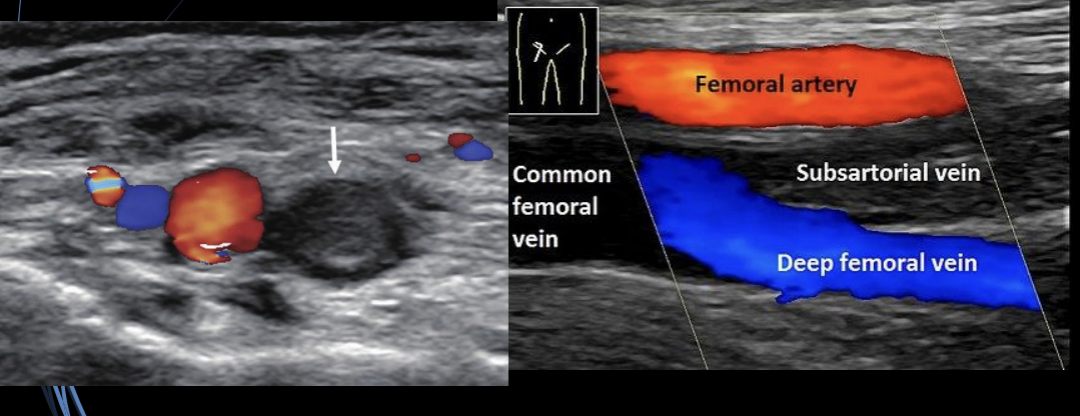

Q

A

Normal

Patologíco

TVP

10

TVO vena subsartorial